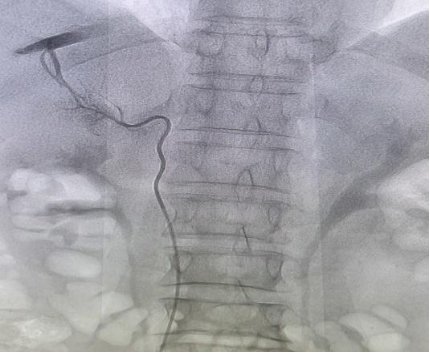

该患者合并COPD及陈旧性肺结核病史,为精准明确病因并评估手术风险,科室启动多学科协作(MDT)讨论。经过各科室专家充分研判,一致建议为患者进行肾上腺静脉采血(AVS)检查,以进一步明确病变性质,同时,呼吸内科及心内科专家综合评估手术风险为中、高危。随后,介入与血管外科团队凭借精湛技术,顺利为患者完成肾上腺静脉采血操作。化验结果显示,左侧肾上腺醛固酮及皮质醇值较右侧明显异常升高,最终确诊该患者疾病为“原发性醛固酮增多症合并亚临床型皮质醇增多症”。明确诊断后,新城院区泌尿外科医疗团队立即为患者开展充分的术前准备工作。手术环节中,麻醉科团队全程保障麻醉过程平稳安全;新城院区泌尿外科主任马渊指导,副主任医师魏晨阳操作成功为患者实施经腹腹腔镜下肾上腺切除术。术后,患者安全返回病房,经过精心护理,目前血压已趋于平稳,恢复状况良好。